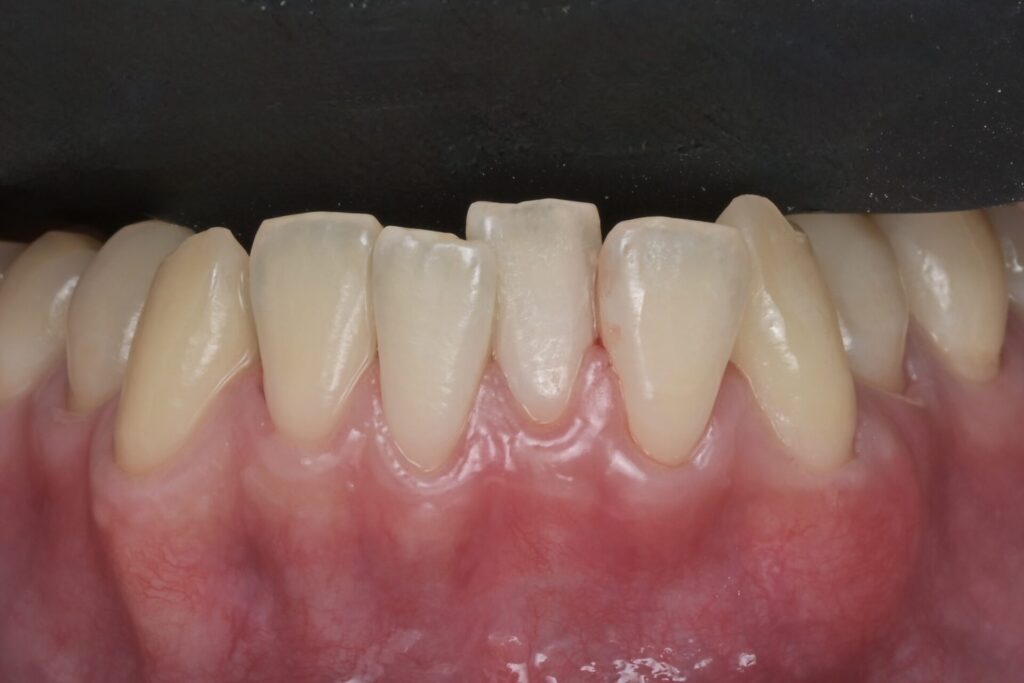

「歯茎下がり」を根面被覆術で治療 30代男性 下顎犬歯部

05根面被覆術

根面被覆術(こんめんひふくじゅつ)は、露出した歯の根を自分の組織で覆い、歯茎の厚みと高さを取り戻す治療です。「歯が長くなった」「老けて見える」といった見た目の改善だけでなく、知覚過敏や将来の根面虫歯のリスクを根本から解消します。